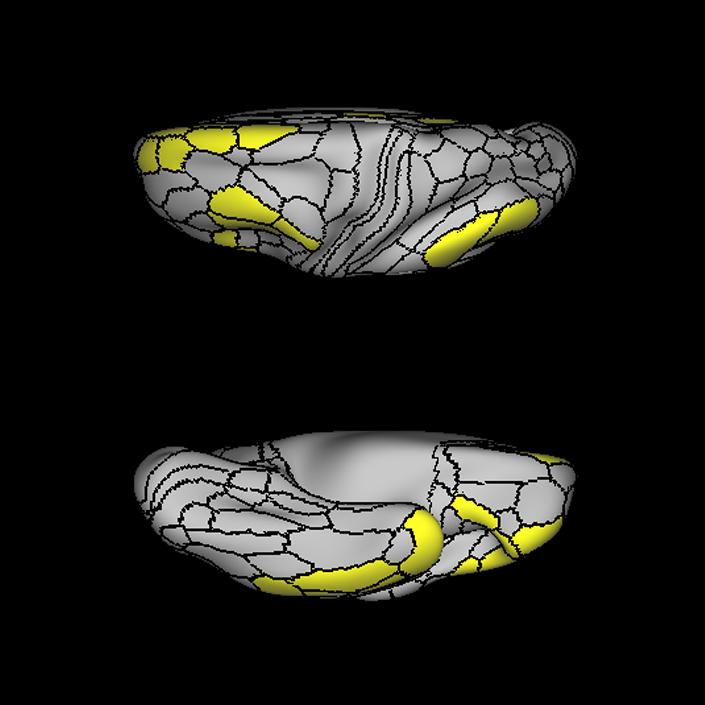

ᐅ SummaryArea 45: part of the inferior frontal gyrus of the lateral frontal lobe. In addition to its known association with Broca's area, is sometimes represented as part of Broca's complex ᐅ Where is it?Area 45 is the lateral surface of pars triangularis of the IFG. ᐅ What are its borders?Area 45 borders area 47L anteriorly and area 44 posteriorly. Its superior edge borders area p47r, IFSa, and IFSp. Its opercular surface is conveniently named FOP5 ᐅ What are its functional connections?Area 45 demonstrates functional connectivity to areas SFL, IFSp, 44, a47r, 47s, 47L, 9a, 9p, 9m, 8AV, and 8BL in the dorsolateral frontal lobe, area 8BM in the medial frontal lobe, area 55b in the premotor areas, areas FOP5, and PSL in the insula-opercular region, areas TGd, TGv, TE1a, STSva, STSdp and STSvp in the temporal lobe, area PGi in the inferior parietal lobe, and area 31pd in the medial parietal lobe. ᐅ What are its white matter connections?Area 45 is structurally connected to the arcuate/SLF and IFOF. However, arcuate/SLF connections are not consistent across individuals. Connections with the arcuate/SLF project posteriorly and wrap around the Sylvian fissure to the middle temporal gyrus to end at TE1p. There are also projections from the arcuate/SLF before it terminates to parcellations A4 and PBelt. IFOF connections travel from 45 through the extreme/external capsule and continue posteriorly through the temporal lobe to end at occipital lobe parcellations V1, V2, V3 and V4. Local short association bundles connect with 44 and FOP4. ᐅ What is known about its function?Area 45, in addition to its known association with Broca's area, is sometimes represented as part of "Broca's complex", including Brodmann Areas 45, 46, 47 and the mesial supplementary motor area of 6, which contribute to a frontal-subcortical circuit. |

A: lateral-medial

B: anterior-posterior

C: superior-inferior

DTI image |